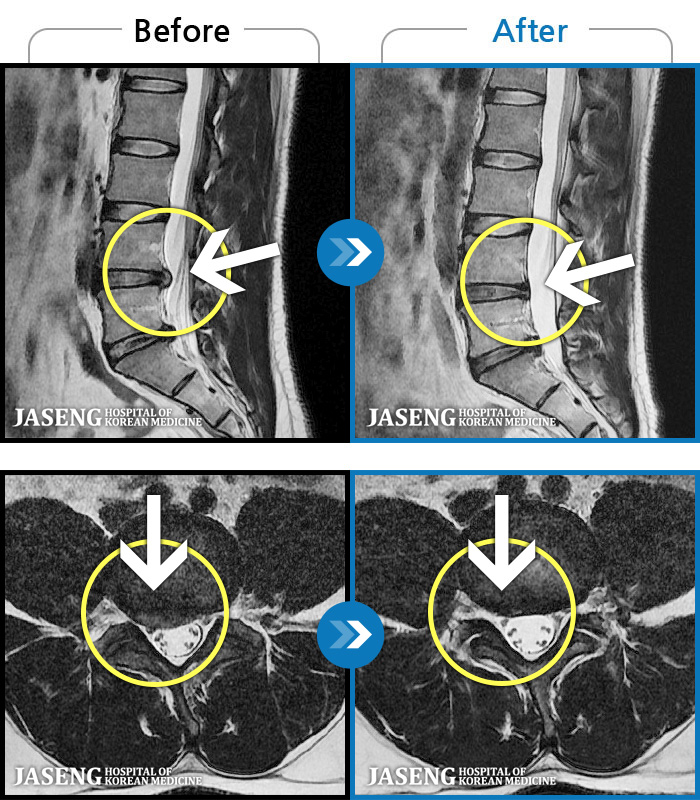

• 허리디스크